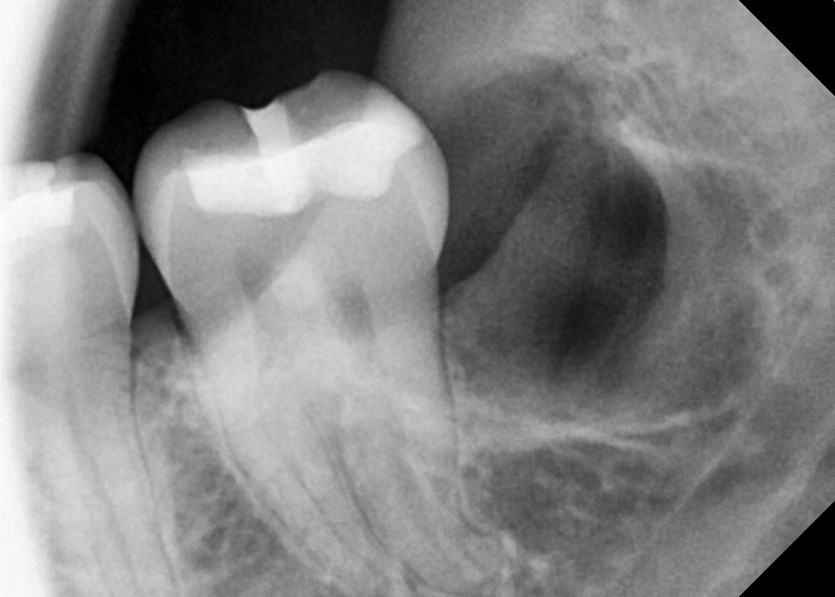

#38,48 사랑니 발치

구강 외과 전문의가 당일 발치했습니다.